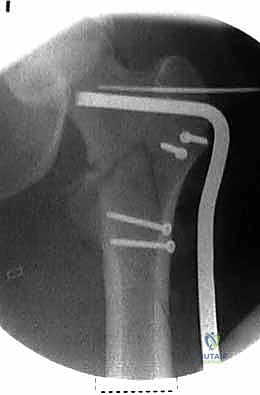

| وجه المقارنة | الشريحة والمسمار المنزلق (DHS - Dynamic Hip Screw) | المسمار النخاعي القريب (PFN - Proximal Femoral Nail) |

|---|---|---|

| آلية العمل | شريحة معدنية تُثبت على السطح الخارجي للعظم مع مسمار كبير يخترق عنق الفخذ. | مسمار من التيتانيوم يُدخل داخل التجويف النخاعي للعظم (من الأعلى) مع مسامير عرضية للتثبيت. |

| نوع الكسور المناسبة | الكسور المستقرة (Stable Fractures) ذات التفتت البسيط. | الكسور غير المستقرة (Unstable)، المفتتة بشدة، أو التي تمتد لأسفل العظم. |

| الشق الجراحي | شق جراحي جانبي أطول نسبياً (حوالي 10-15 سم). | جراحة طفيفة التوغل، شقوق صغيرة جداً (Minimally Invasive). |

| الميكانيكا الحيوية | يوفر ضغطاً ديناميكياً ممتازاً على موقع الكسر أثناء المشي. | يوفر دعماً ميكانيكياً أقوى لأنه يقع في مركز ثقل العظم (محور تحمل الوزن). |

| فقدان الدم | أكثر نسبياً مقارنة بالمسمار النخاعي. | أقل بكثير. |

| سرعة التعافي | ممتازة، ولكن قد تتطلب حذراً أكبر في الكسور غير المستقرة. | أسرع، ويسمح بتحميل الوزن في وقت أبكر في الحالات المعقدة. |

مجموعة من الصور الإضافية التي توضح مراحل دقيقة من العمل الجراحي المعقد الذي يجريه الأستاذ الدكتور محمد هطيف لضمان أعلى درجات الدقة الميكانيكية الحيوية: